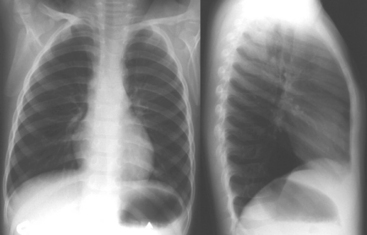

Airflow obstruction results from decreased airway caliber, which causes increased resistance to the flow of both inspired and expired gas. However, exhalation is predominantly affected. Mucus plugging within the small airways results in air trapping and hyperinflation of the lungs, causing the diaphragm to be flattened instead of a typical dome shape at rest92 (Fig. 9-8).

image

Fig. 9-8 Chest radiographs of a patient with hyperinflation. No infiltrates are noted. The right side is more radiolucent (darker) compared with the left. This is subtle and may be difficult to appreciate unless the chest radiograph is viewed from a distance. The right hemidiaphragm is normally higher than the left hemidiaphragm; they are at about the same level in this patient. These findings suggest hyperinflation of the right lung. The clinical history indicated that the child was jumping on a bed while eating a snack, when she began choking. Since that time, she has experienced respiratory difficulty. Further radiographs revealed bilateral air trapping. Bronchoscopy revealed bilateral bronchial peanut fragment foreign bodies. Impression: Right-sided hyperexpansion and air trapping, which may represent a bronchial foreign body.